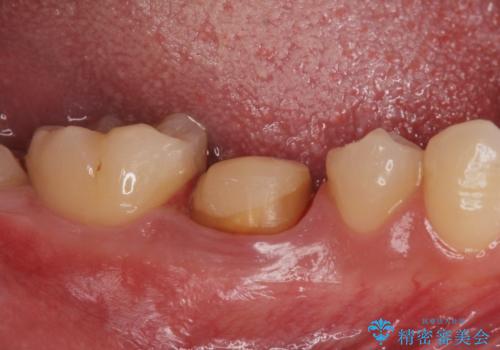

- 古い被せ物が取れたとの事で来院。

過去に根管治療がされている歯でしたが、現在症状はなく、レントゲンでも根尖病巣がないが根尖まで薬が到達していない状態でした。

そのまま被せ物だけやりかえるか根尖病巣の再発のリスクを考えて再根管治療を行うか患者様に決めて頂きました。

被せ物だけの治療を選択されましたのでジルコニアクラウンでの治療を行いました。